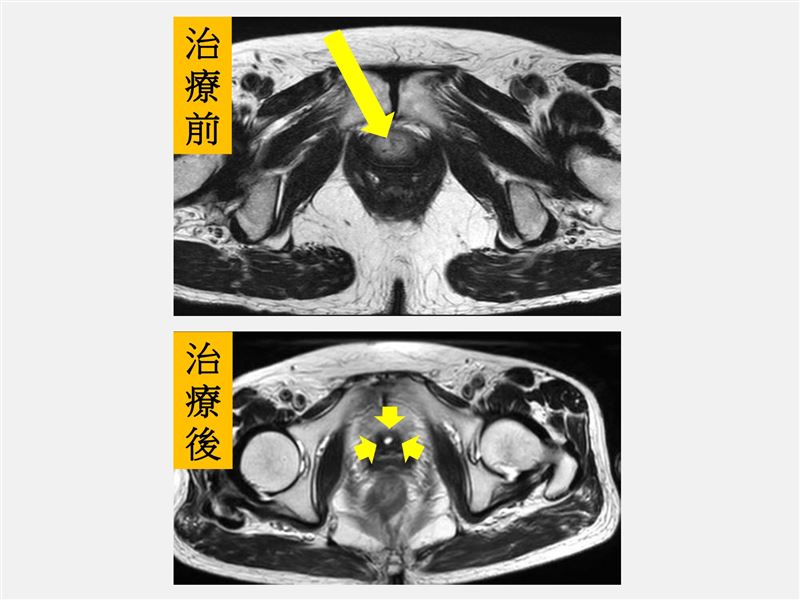

經放療與化療治療後,經核磁共振掃描發現尿道已無腫瘤。(圖/仁愛長庚醫院提供)

放射腫瘤科盧皓維主任表示,患者腫瘤侵犯範圍廣泛,若直接進行手術切除,恐將影響正常泌尿道功能,決定轉介到血液腫瘤科,共同規劃治療策略,爭取泌尿道器官保存的可能性。經跨科團隊充分討論後,最終決定採取根治性同步化學放射治療,以尿道腫瘤作為主要照射目標,由於病灶位置鄰近外陰部的敏感皮膚區域,治療期間一度出現中度以上的放射線皮膚炎及泌尿道發炎等副作用,順利結束療程後,副作用已恢復,且追蹤檢查顯示腫瘤已消失,治療成效良好。